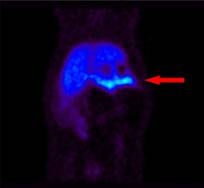

A preclinical study presented by Dr. Mei-Ping Kung of the University of Pennsylvania in Philadelphia on the use of Avid Radiopharmaceuticals' compound AV-133 (18F-FP-DTBZ) was selected as the 2007 Small Animal Image of the Year at the 2007 SNM meeting.

The study showed that AV-133, a molecular imaging agent targeting the vesicular monoamine transporter-2 (VMAT2), is potentially useful for measurement of beta cell mass and for studying the pathogenesis of diabetes.

The PET image of a rat pancreas follows injection with AV-133. Researchers at the University of Pennsylvania and University of Michigan discovered the compound. It is currently under investigation at Avid, a Philadelphia-based radiopharmaceutical company.